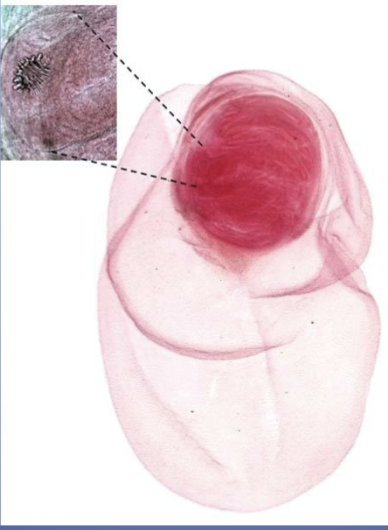

Taenia pisiformis cysticercus

Tapeworm cysticercus larva

Larval stage found in muscle and/or viscera of worm IH

Hooks are hard to see, but are visible in the photo